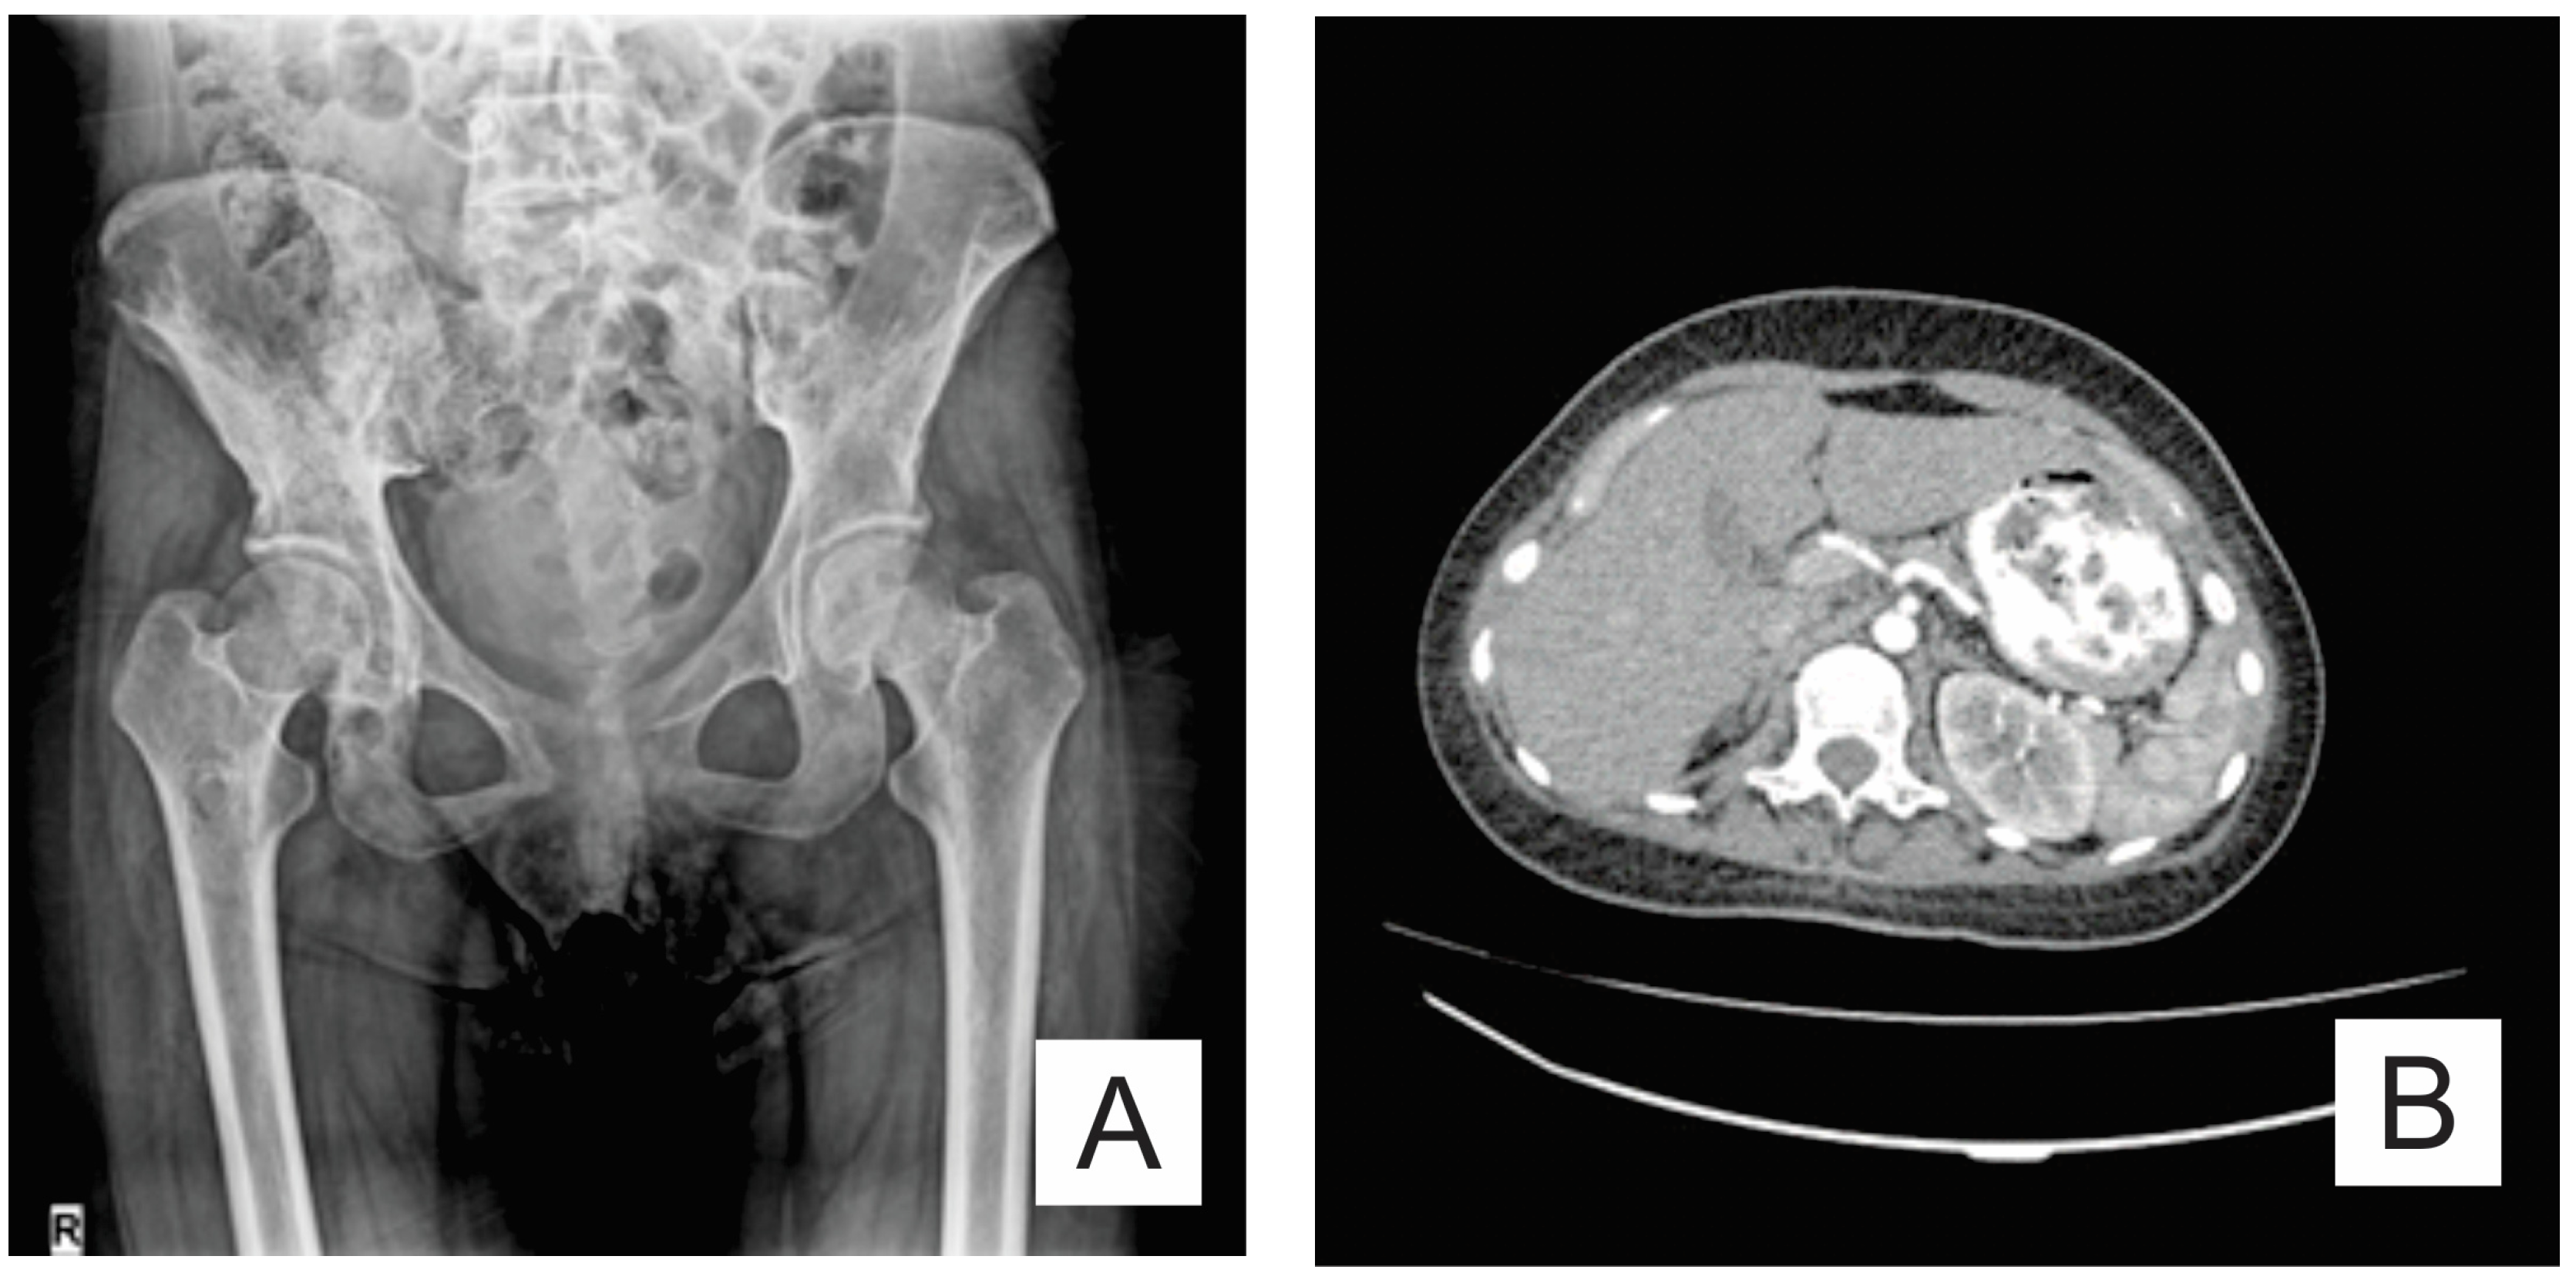

2. Case Report